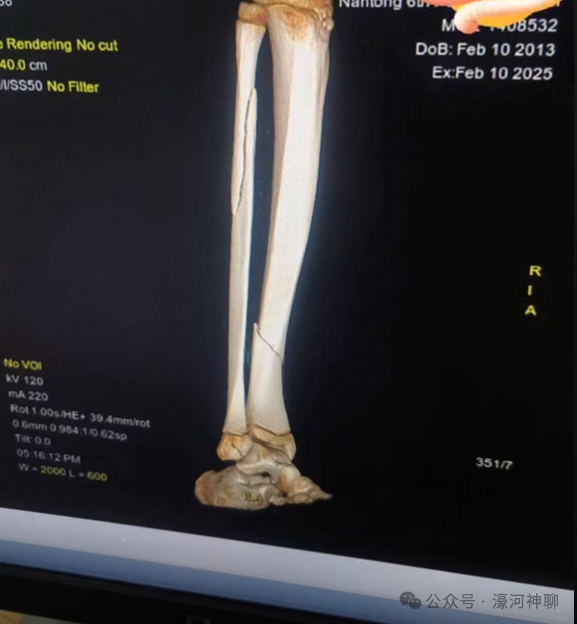

玩儿“沙滩车”项目摔断了腿

孩子现在开了刀放了钢板

还要二次手术取钢板

看片子,骨头都断开错位了,挺严重了,这不是脱臼,也不是骨裂,是断裂并错位。孩子未成年,骨头还在生长,已经错位的骨头不拼合起来再生长,后面有一大堆问题。真信你的话就有问题了。中药不是万能的,有些该手术的还是要依赖手术。